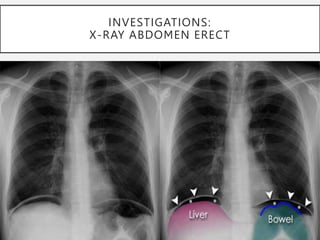

INVESTIGATIONS:

X-RAY ABDOMEN ERECT